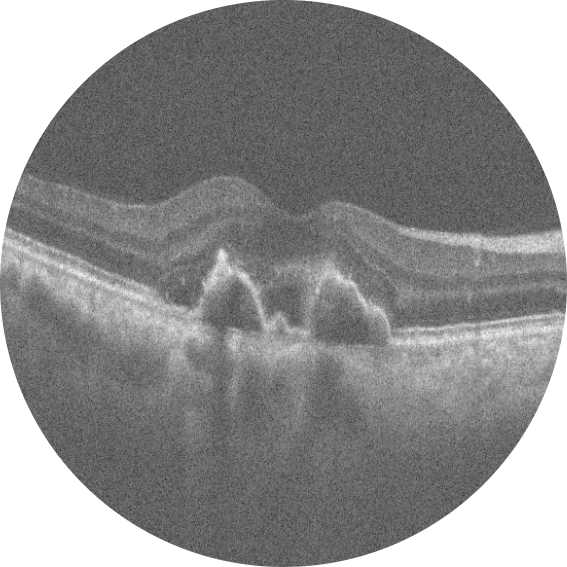

Kliniğimize her iki gözde çocuk yaştan bu yana gittikçe artan görme azlığı şikay ...

Optik pit ve seröz makula dekolmanı nedeniyle pars plana vitrektomi ve arka hyal ...